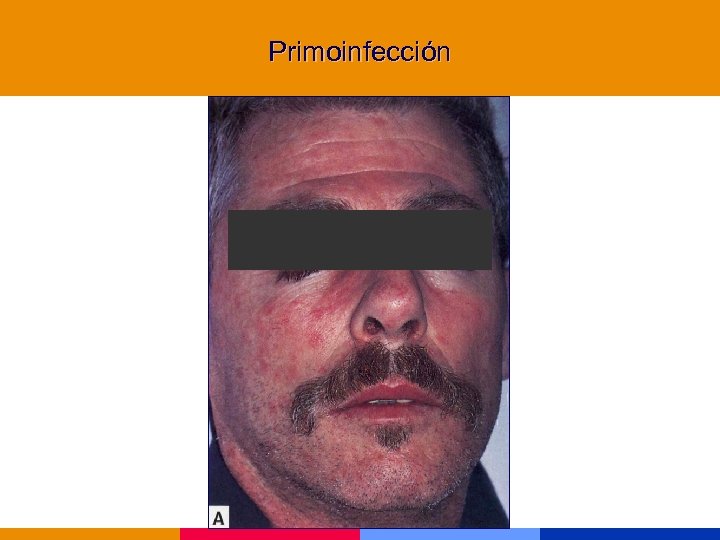

Primoinfección

Primoinfección

Primoinfección

Primoinfección

Primoinfección

Primoinfección

Primoinfección

Primoinfección